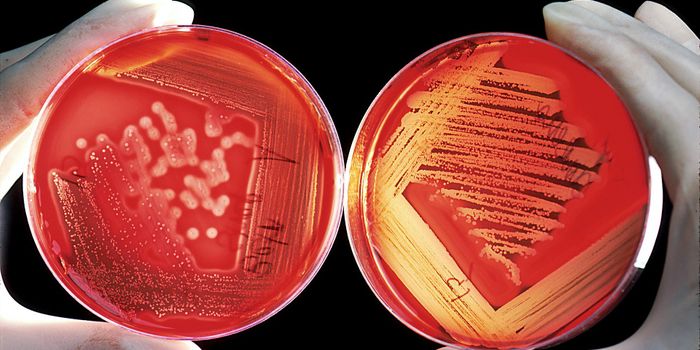

FEB 01, 2016MicrobiologyTo most of us “virulent” means “aggressive,” or just plain “bad,” but to a microbiol ...

OCT 05, 2016MicrobiologyMicroorganisms frequently attach to a surface and begin to grow into a colony called a biofilm in which cells stick to e ...

JUL 08, 2017MicrobiologyDoctors and researchers have been sounding the alarm about drug-resistant gonorrhea, and it is spreading around the worl ...

MAY 19, 2017MicrobiologyCandida auris is often resistant to most antibiotic treatments.

MAY 20, 2024MicrobiologyThis article is the third in Microbiologics’ series on Optimal QC in the Clinical Laboratory. Previously, in this ...